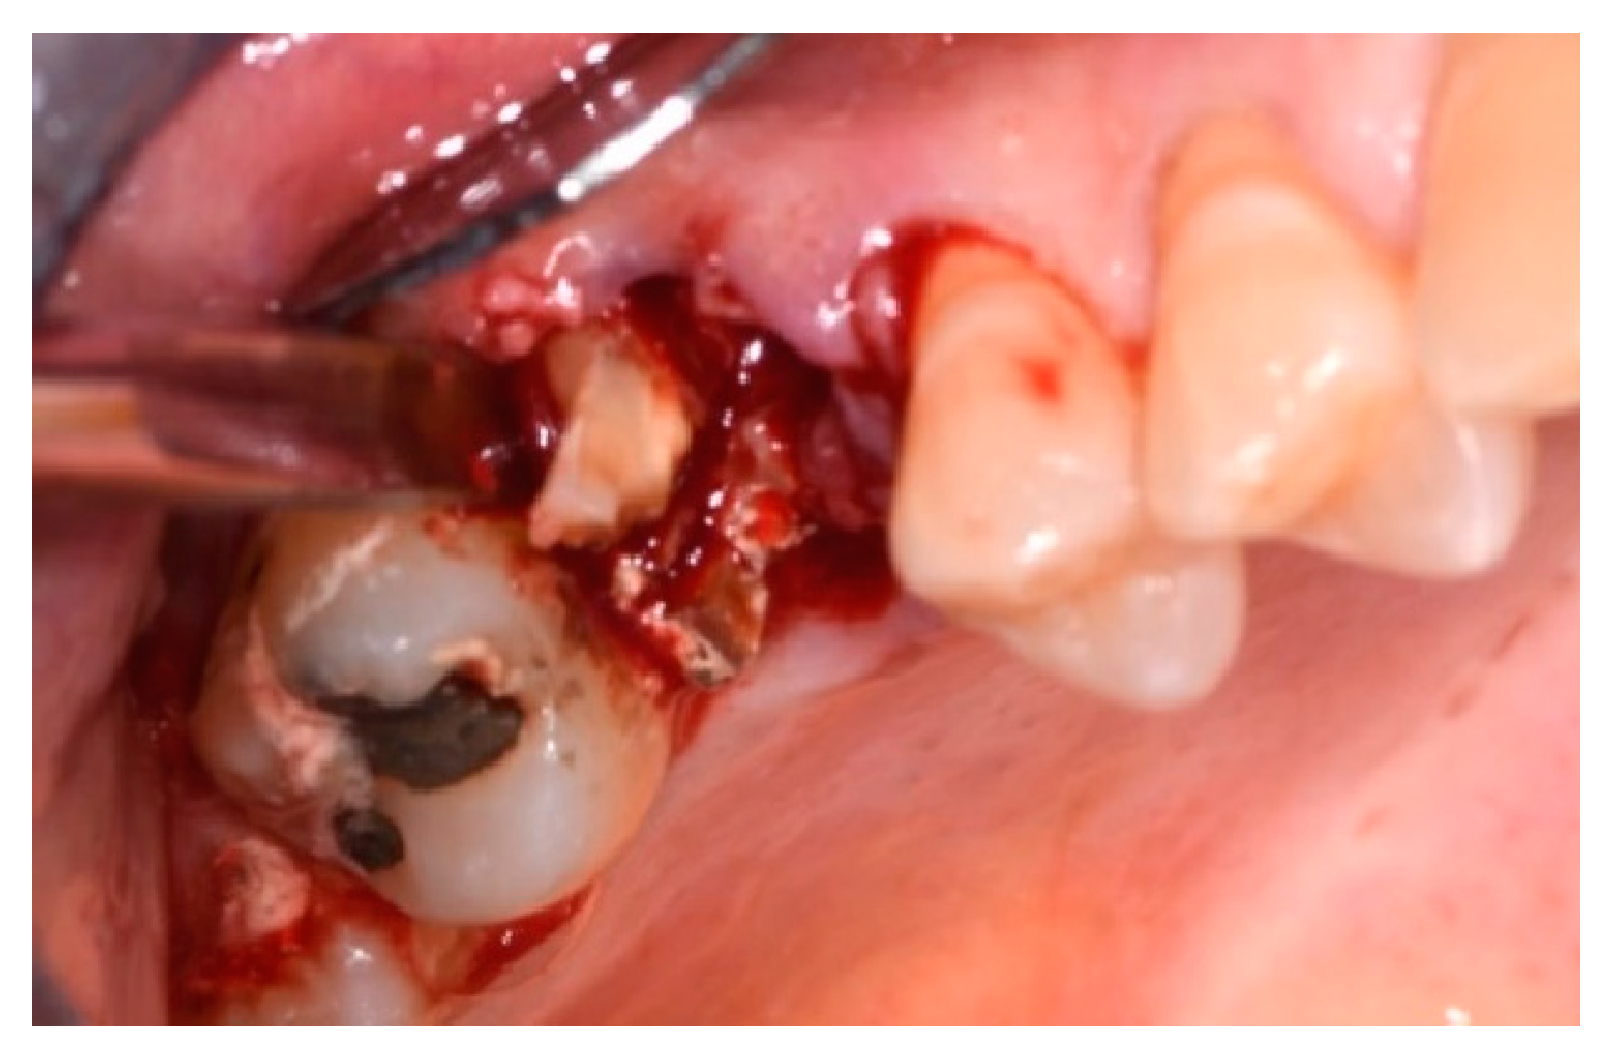

- Use of Magnetic Mallet® inserts and extraction pliers only;

- Use of inserts, pliers, and hand levers;

- Time of the extraction considered between the end of anesthesia and the avulsion of the element;